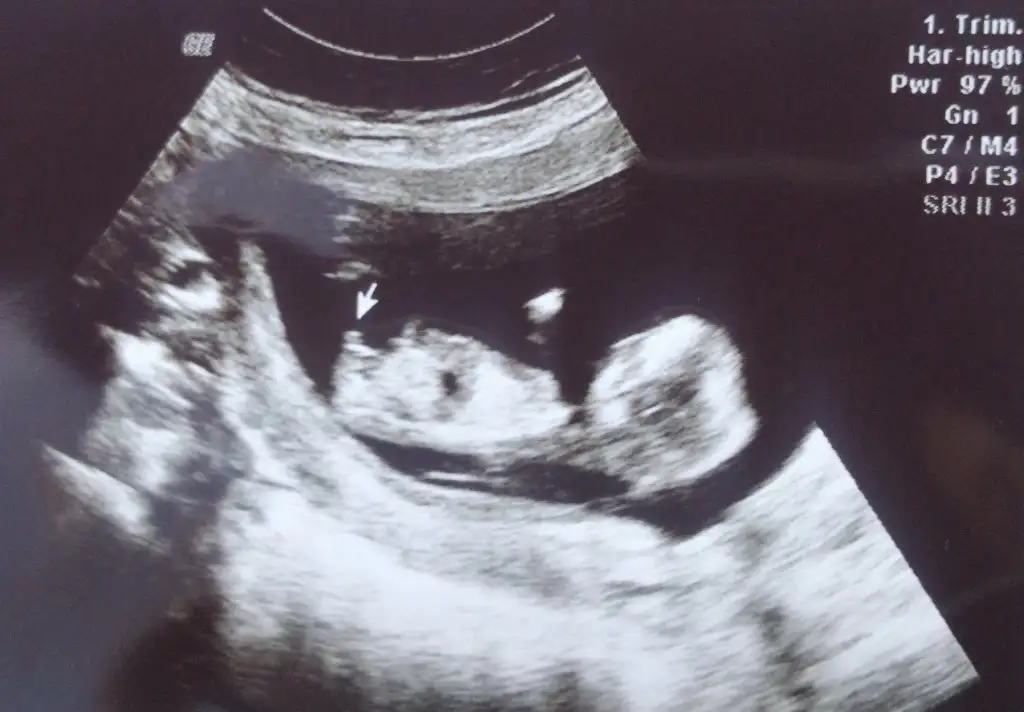

10+6 nub teorisine gore cinsiyeti nedir 🤗